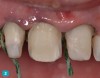

A 22-year-old female patient was referred to the University of North Carolina’s Graduate Prosthodontic Clinic by her hometown dentist in New York. She had been involved in a sports-related accident and had fractured off a large portion of teeth Nos. 7 and 9 and also fractured tooth No. 8 (Figure 1). The dentist discussed treatment options with the patient, including a single-appointment CAD/CAM process with full ceramic crowns and veneers. Properly placed digitally designed and milled restorations have been extremely successful with proper preparations and occlusal design considerations. The patient came in that day for a single preparation and seat appointment. The 3 teeth were prepared for the all-ceramic restorations, following accepted CAD/CAM glass-ceramic preparation guidelines with adequate clearance, rounded internal aspects, and supragingival rounded butt joint margins (Figure 2).

Fig 1. Preoperative condition of fractured teeth.

Figure 1